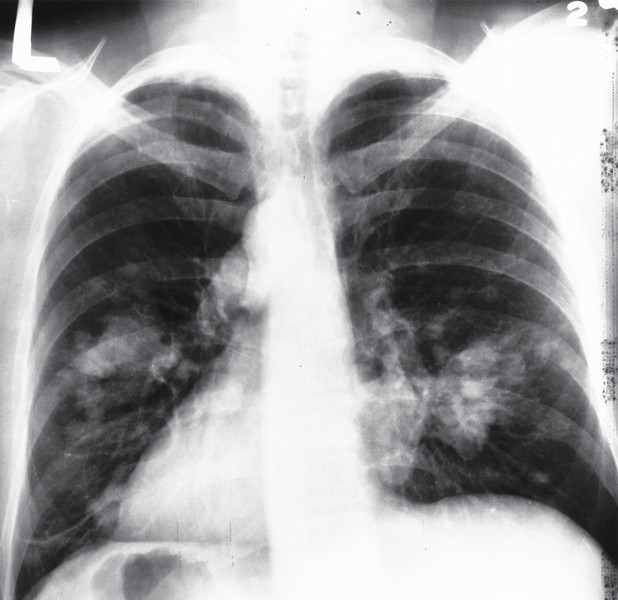

【肺部鱗狀細胞癌化】

非小細胞癌又分為最常見的肺腺癌、未分化大細胞癌,以及男性吸菸者最常罹患的鱗狀上皮細胞癌,約占非小細胞癌患者的3成。目前多認為肺癌係患者長期將香菸主要成份之一的焦油,經燃燒後產生的數十種致癌化學物質直接吸入肺部所致;多從較主要的大支氣管黏膜細胞開始癌化,可能引發支氣管狹窄、肺塌陷、阻塞性肺炎、肺氣腫及肺部組織纖維化,部分患者會出現咳血症狀。

倫敦癌症研究中心團隊比對1萬1千餘名歐洲肺癌患者,以及1萬5千多名健康者的基因序列後發現,約有16%的男性吸菸者及近1成的女性吸菸者罹患肺癌,其中約4分之一的BRCA2基因突變吸菸者罹患肺部鱗狀上皮細胞癌;該研究主持人、分子基因學教授里查豪斯登表示,吸菸者體內若帶有突變的BRCA2基因,罹患肺部鱗狀細胞癌的風險是常人的1.8倍。